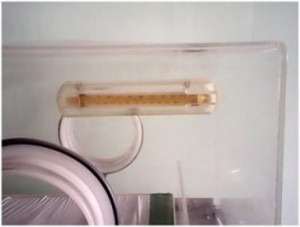

۲٫در نزدیک هیتر، موتوری برای چرخاندن فن تعبیه شده تا هوای تازه را از فیلتر(صافی) گرفته و آن را برای گرم نمودن هوا به پشت هیتر هدایت نماید. که در شکل زیر این فن دیده می شود.در انکوباتورهای جدید فنها مجهز به سنسور القایی(اثرهال) جهت تشخیص چرخش صحیح فن می باشند. در صورتیکه این سنسور حرکت فن را حس نکند دستگاه مانع گرم شدن فن شده و آلارم خرابی دستگاه فعال می شود.

گردش مداوم این فن، هوا را مکیده، وهوا پس از عبور از فیلتر و تصویه آن به داخل می کشد. فیلتر باید هرازگاهی بررسی شود و در صورت کثیف بودن تعویض شود..